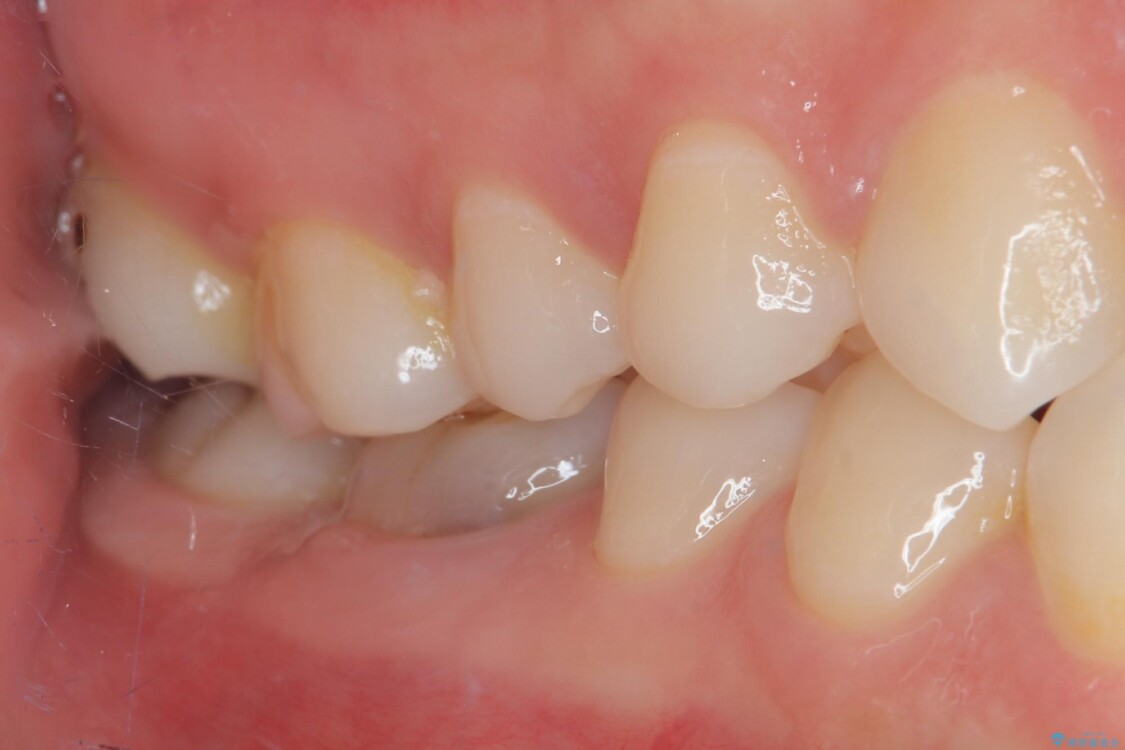

治療後

• ラバーダム使用で再感染リスクを抑えた再根管治療+精密な補綴による長期安定を実現 治療後画像

当院ではラバーダム防湿をし、根管内の感染源をしっかりと除去するために再根管治療を行いました。

その後、ファイバーコア(グラスファイバー製の支台)を築造し、最終的には精密な適合性と審美性に優れたオールセラミッククラウンによる補綴をしました。

このセラミッククラウンは、歯科技工士と連携し、1本1本の形・色・噛み合わせまで細部にこだわって製作しており、見た目の自然さだけでなく、長期的に安心して噛める機能性も重視しています。